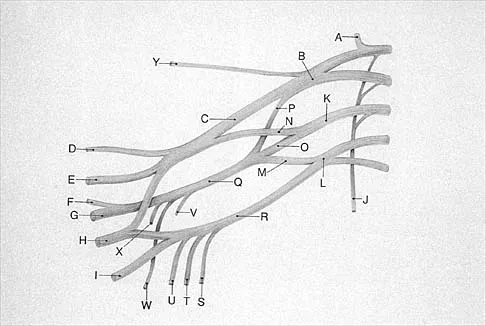

The dorsal digital cutaneous nerve of the great toe shown in Figure 8 is a branch of what nerve?

Options:

- Saphenous

- Medial branch of the superficial peroneal

- Deep peroneal

- Posterior tibial

- Sural

Correct Answer: Medial branch of the superficial peroneal

Explanation:

The dorsal digital cutaneous nerve of the great toe is a branch of the medial branch of the superficial peroneal nerve. The deep peroneal nerve supplies the first web space. McMinn RMH, Hutchings RT, Logan BM: Color Atlas of Foot and Ankle Anatomy. Weert, Netherlands, Wolfe Medical Publications, 1982, p 50.

References:

Gray H: Anatomy of the Human Body. Philadelphia, PA, Lea & Febiger, 2000, pp 963, 966.